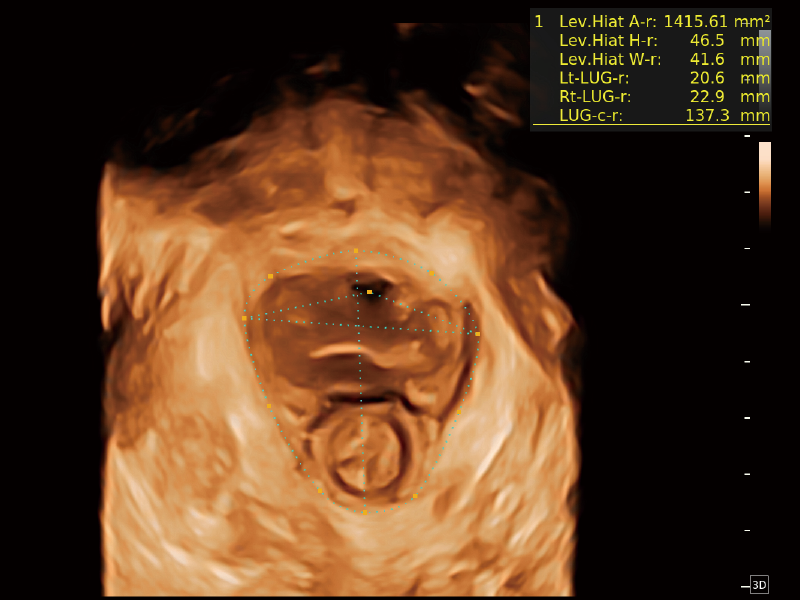

夢(mèng)溪?P80以“關(guān)愛(ài)女性”為基石,提供全方位的解決方案,量身定制以滿足女性的健康需求,涵蓋婦科、生殖健康檢查、產(chǎn)前篩查及產(chǎn)后康復(fù)等領(lǐng)域。